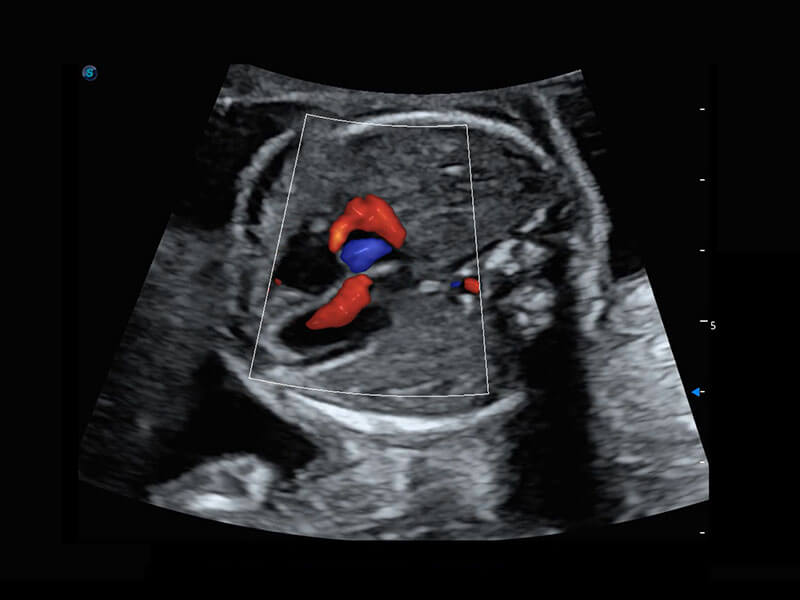

P60搭载一系列胎儿心脏成像技术,实现精细的胎儿心脏评估。

四腔心血流

右室双出口

胎心容积成像